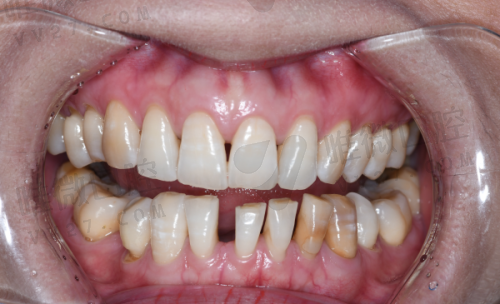

擅长项目:

儿童齿科、龋齿填补、牙冠修复、早期错颌干预

医院优势:

嘉云口腔在儿牙领域有显著优势,配有独立诊室和亲子互动等待区。医生团队对儿童心理有较强了解,能根据孩子配合度选择不同治疗路径,氛围友好不压迫。治疗材质均为安心环保型,确保孩子健康不受影响。